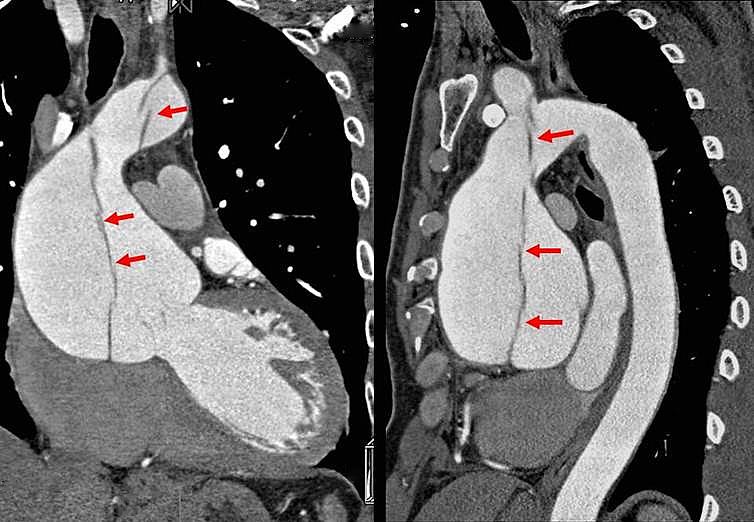

40歲男性罹患主動脈剝離,冠狀動脈攝影電腦斷層影像顯示升主動脈擴大,直徑約82.2mm,主動脈內膜剝離(箭頭)至主動脈弓,幸好冠狀動脈未受影響。文獻統計,主動脈剝離患者3%立即死亡,20%~30%在24小時內死亡。